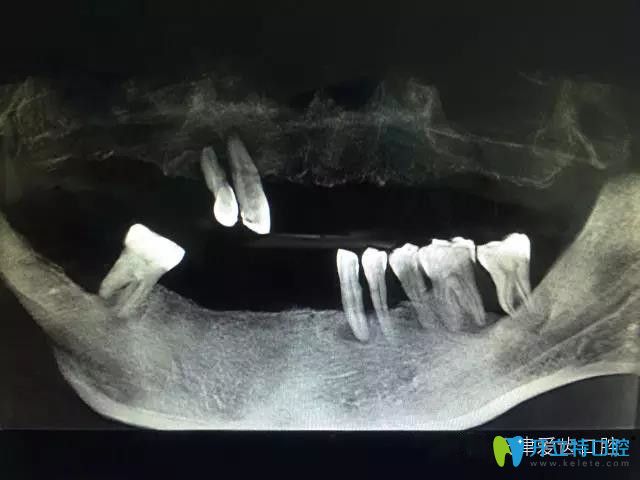

擅長(zhǎng)項(xiàng)目:即拔即種的即刻種植技術(shù)、all-on-4無(wú)牙頜即刻種植修復(fù)技術(shù)、各種種植骨增量、骨移植、上頜竇內(nèi)外提升等復(fù)雜種植技術(shù)等;復(fù)雜智齒拔除術(shù)、牙體牙髓病治療、牙周病治療等。

周航,天津口腔系畢業(yè),從事口腔臨床工作臨床30多年,種植經(jīng)驗(yàn)20多年,現(xiàn)任天津愛(ài)齒口腔集團(tuán)種植外科醫(yī)生、全科醫(yī)生。曾赴德國(guó)、韓國(guó)等國(guó)內(nèi)外口腔醫(yī)療機(jī)構(gòu)進(jìn)修學(xué)習(xí)口腔種植新技術(shù),尤其擅長(zhǎng)即刻拔牙即刻種植技術(shù),是較早在天津開(kāi)展即刻種植及無(wú)牙頜即刻種植修復(fù)的醫(yī)生之一。